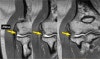

4. Os supratrochlear dorsale

An accessory ossicle of the elbow located in the olecranon fossa of the humerus.

It may become symptomatic due to trauma during elbow extension and as such may require surgical removal.

The differential diagnosis is an intra-articular loose body but the treatment if symptomatic remains the same.